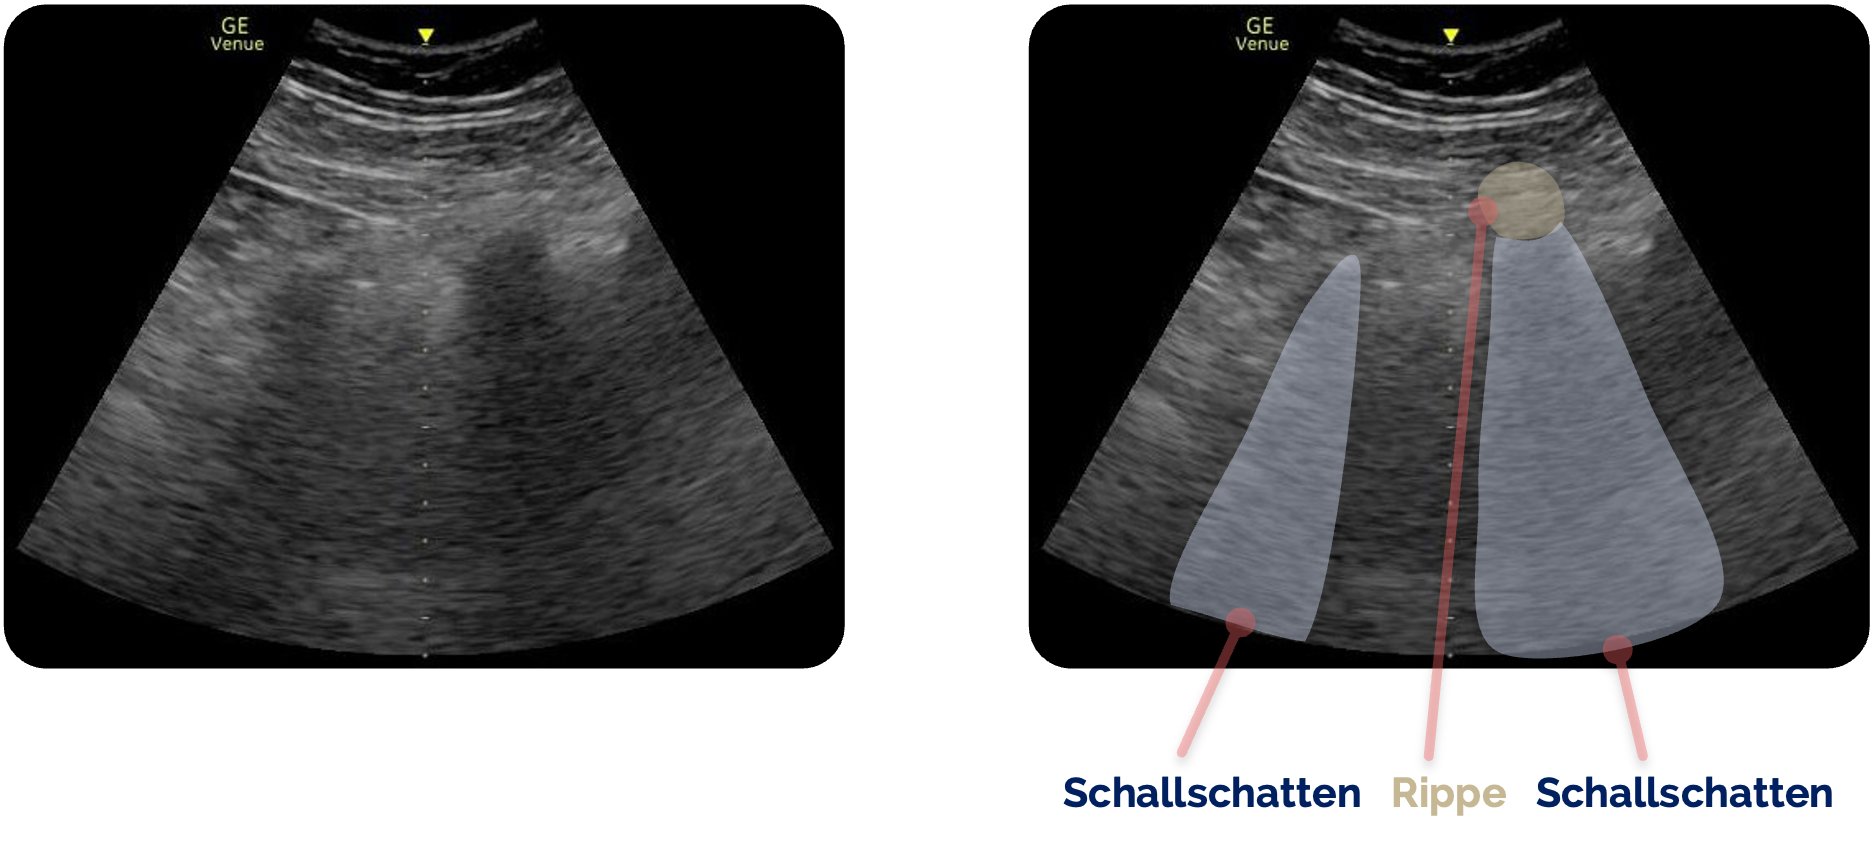

Schallschatten:

Ein Schallschatten suggeriert, dass hinter einer Struktur keine weiteren Informationen erfasst werden können. Das Prinzip entspricht einem Lichtstrahl, der auf ein Hindernis trifft. Bei dichten Strukturen wie Knochen wird der eintreffende Schall nahezu vollständig absorbiert oder reflektiert, sodass kein Signal in die tiefer liegenden Bereiche gelangt. Es entsteht ein „blinder Bereich“ im Bild. Typische Beispiele sind die Rippenbögen, die den Einblick auf darunterliegende Organe erschweren. Gleichzeitig kann ein Schallschatten jedoch diagnostisch wertvoll sein, etwa bei Gallen- oder Nierensteinen sowie bei Fremdkörpern, da diese Strukturen charakteristische artifizielle Schatten erzeugen.

Schallschatten der Rippen links und rechts der Bildmitte